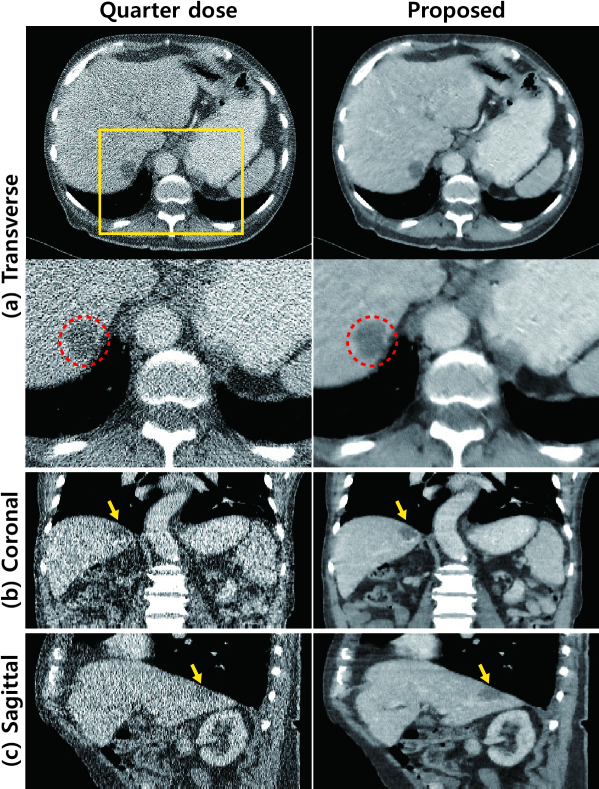

Refer to caption

Figure 9: X-ray CT images from test data set ‘L057’. Quarter-dose images are in the first column and denoised images using the proposed algorithm are in the second column. (a) Transverse images. Enlarged images within the yellow box in the second row. The lesion is marked by red dashed circles. (b) Coronal images and (c) Sagittal images. Yellow arrow indicate the lesion. The intensity range was set to (-160,240) [HU] (Hounsfield unit).

Fig. 9 shows the denoised images of data from one patient from among the 20 patients with only quarter-dose data. The trained network is applied to the test data and its denoising performance is demonstrated by the determination of the location of the lesion, as indicated by the red dashed circle. The coronal and sagittal presentation of the results is also shown in Fig. 9. Yellow arrows indicate the location of the lesion, providing a better view to assist with the understanding of the condition of the patient.